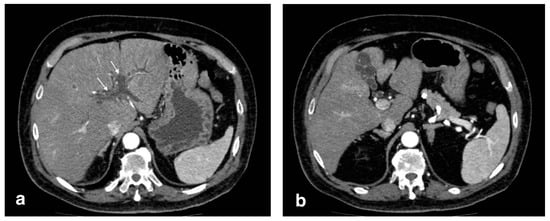

2.1. CT Findings in Acute Cholecystitis

Despite being less sensible than US in diagnosing acute cholecystitis, CT has proven to be essential for differential diagnosis or in patients with atypical clinical presentation. The most common features include diffuse mural thickening, gallbladder distension, pericholecystic fluid, and pericholecystic fat stranding [7] (Figure 1). A transient enhancement rim in the adjacent liver is a common finding. Despite that, CT is less sensible than US in finding gallstones, even of large dimensions in some cases [8]. In addition, mural thickening is a poorly specific criterion for diagnosis alone, as it is seen in a variety of other conditions, such as hepatitis, hypoproteinemia, heart failure, and acute pyelonephritis [9]. Acalculous cholecystitis occurs with the same CT findings, in the absence of gallstones; this form has a higher chance to develop complications (such as gangrenous cholecystitis and perforation) [6].

Figure 1.

Acute uncomplicated calculous cholecystitis: (a) overdistended gallbladder with diffuse wall thickening and hyperemia (white arrows) and pericholecystic fluid (arrowheads), (b) pericholecystic parenchymal enhancement (black arrows).